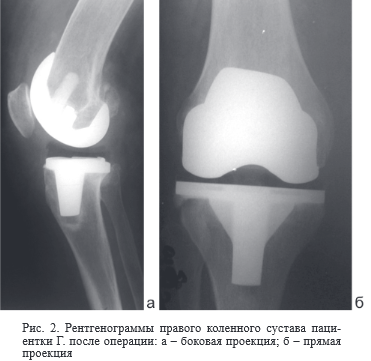

В анамнезе 12. 05. 2011 года по поводу правостороннего гонартроза, варусной деформации правого коленного сустава было выполнено первичное эндопротезирование правого коленного сустава эндопротезом с сохранением задней крестообразной связки (CR). Ниже представлены рентгенограммы правого коленного сустава до операции (рис. 1) и после операции эндопротезирования (рис. 2).